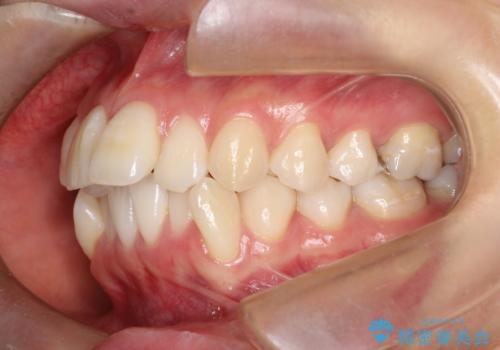

- 出っぱによる口元の閉じにくさを主訴に来院されました。上顎の出っ歯と上下顎叢生も認められたため、上下顎両側4番抜歯を行い、ワイヤー矯正で治療する治療計画を立てました。

上顎にはMI(マイクロインプラント)を埋入して固定源とすることで出っ歯の改善を図りました。

少しスペースクローズに時間がかかりましたが、MIを用いたワイヤー矯正で

主訴である出っ歯と叢生が改善されました。口も閉じやすくなり、スッキリとした口元になりました。